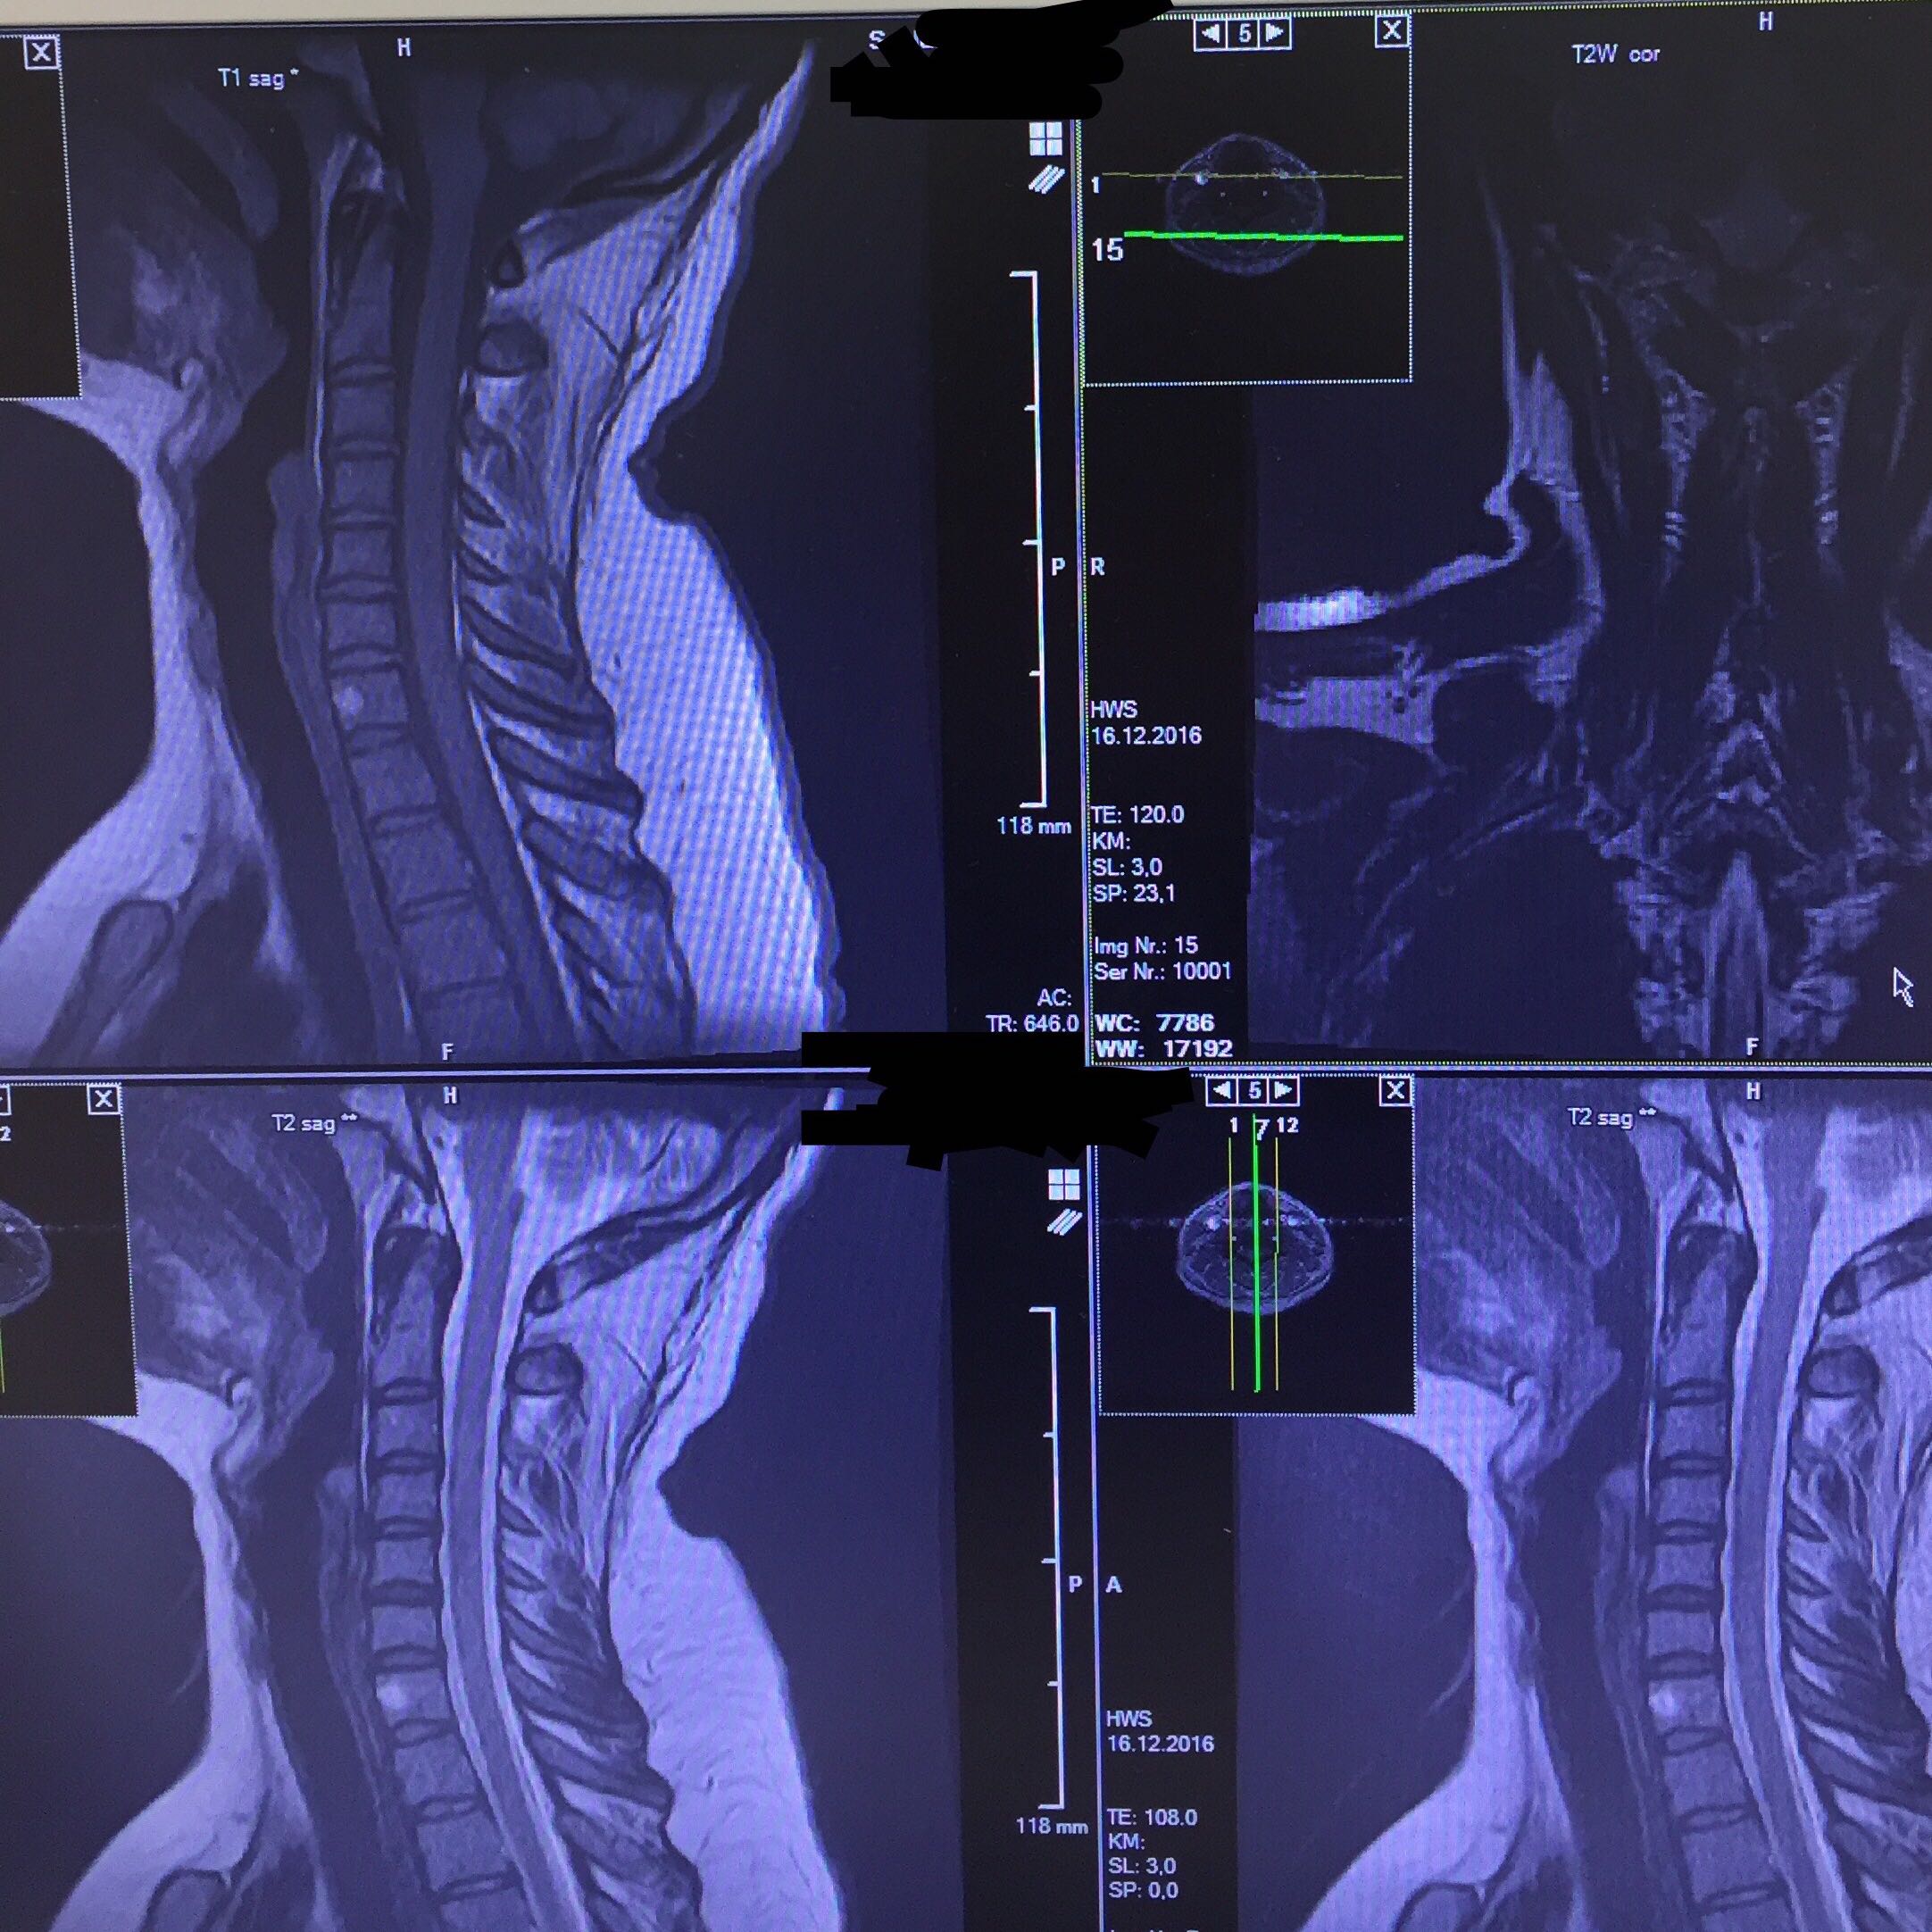

The two basic types of MRI images are T1weighted and T2weighted images, often referred to as T1 and T2 images On T1 images FAT is white On T2 images both FAT and WATER are white. MRI of the Cervical Spine, sagittal T2weighted image 1, Lateral mass of C1 (atlas) 2, Posterior arch of C1 3, Vertebral foramen with cerebrospinal fluid 4, Spinous process of l'axis Image 12 MRI of the Cervical Spine, sagittal T2weighted image 1, Vertebral foramen Cerebrospinal fluid. T1 und T2 sind entscheidend für den Bildkontrast Bei einer T1Gewichtung gibt es andere Bilder als bei einer T2Gewichtung (bei B0=1,5T) T1 (ms) 870 490 650 780 260 >4000 0 T2 (ms) 47 43 58 67 84 >00 79 Skelettmuskel Leber Niere Milz Fett Liquor Lunge Abb 7 T1 und T2Relaxation Abb 8 T1/T2 in verschiedenen Medien T1Relaxation.

T1 und T2 sind entscheidend für den Bildkontrast Bei einer T1Gewichtung gibt es andere Bilder als bei einer T2Gewichtung (bei B0=1,5T) T1 (ms) 870 490 650 780 260 >4000 0 T2 (ms) 47 43 58 67 84 >00 79 Skelettmuskel Leber Niere Milz Fett Liquor Lunge Abb 7 T1 und T2Relaxation Abb 8 T1/T2 in verschiedenen Medien T1Relaxation. MRI of the Cervical Spine, sagittal T2weighted image 1, Lateral mass of C1 (atlas) 2, Posterior arch of C1 3, Vertebral foramen with cerebrospinal fluid 4, Spinous process of l'axis Image 12 MRI of the Cervical Spine, sagittal T2weighted image 1, Vertebral foramen Cerebrospinal fluid. T2 bright/highintensity signal, usually greater than on T1, due to its high water content T1 C significant enhancement is seen due to high vascularity;.